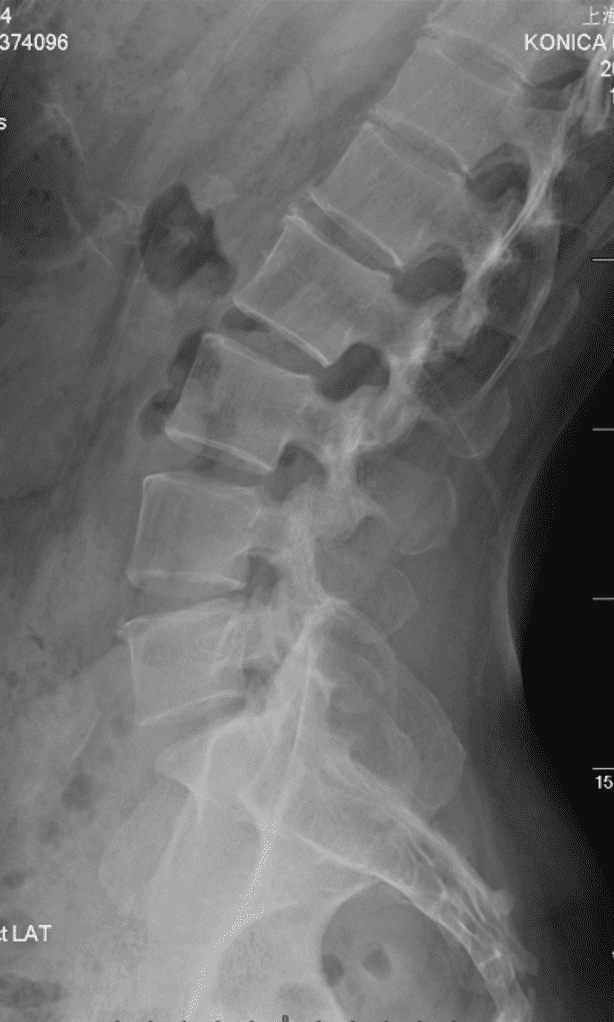

UNet 精确标记例

约 4000 例 Sagittal X-Ray 图片训练,使用 HRNet ,输出线性标记直接分类预测椎点。

- 骨架:采用 HRNet (High-Resolution Network) 作为主干,保持多尺度并行高分辨率流并在阶段间反复交换信息,提升对位置敏感任务(关键点定位、线段化)的空间精度。参考:Wang et al., arXiv:1908.07919。